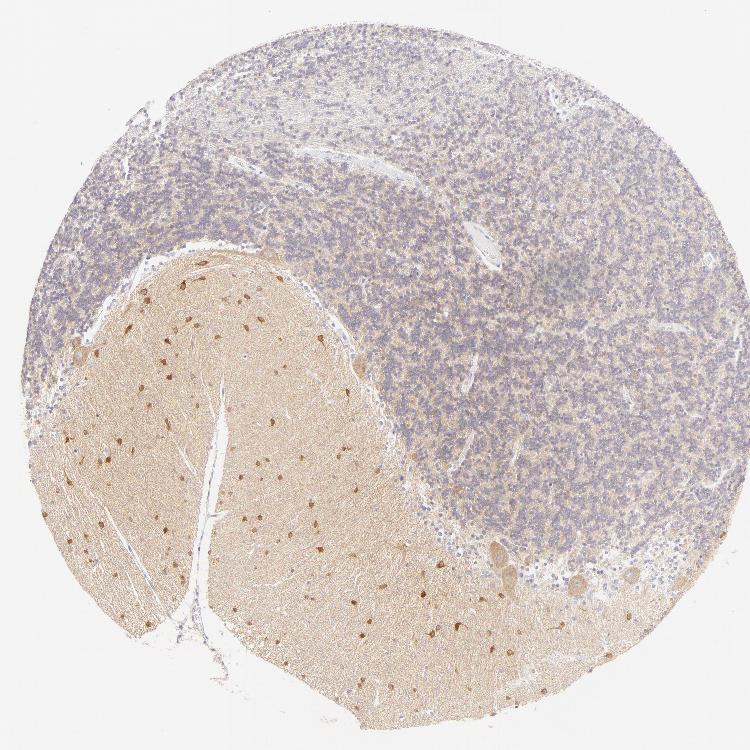

CEREBELLUM - Antibody stainingi

Antibody staining in the annotated cell types in the current human tissue is reported as not detected, low, medium, or high, based on conventional immunohistochemistry profiling in selected tissues. This score is based on the combination of the staining intensity and fraction of stained cells.

Each image is clickable and will lead to virtual microscopy that enables deeper exploration of all samples and also displays staining intensity scores, fraction scores and subcellular localization as well as patient and tissue information for each sample.

Antibody HPA010122Antibody HPA071006Antibody CAB001999Antibody CAB002000

Purkinje cells MediumNot detected-High

Cells in granular layer Not detectedMedium-Medium

Cells in molecular layer HighHigh-High